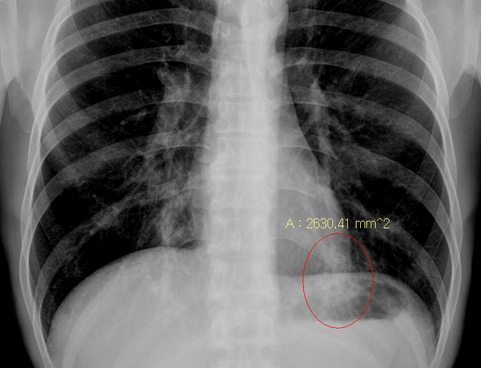

청진음은 폐첨부에 rhonchi 양상이긴 하였으나 x-ray상 Lt. posterior basal segment에 air bronchogram이 관찰됨; 가래 배양 검사등 시행 후 항생제 투여하고 외래 추적 예정